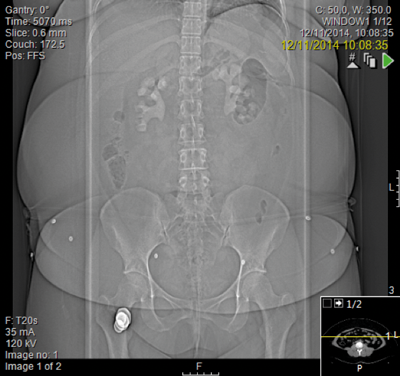

A general practitioner ultrasound was performed on a 29-year-old woman which hinted at bilateral stones. She gave a history of urinary tract infections throughout her pregnancy but had no paediatric history of note. She weighed 105kg with a body mass index (BMI) of 43 and was chronically anaemic with a haemoglobin of 97 and a creatinine of 186 and urine colonised with E. coli.

Following discussion at an X-ray meeting and a nephrology opinion, a left-sided percutaneous nephrolithotomy (PCNL) was performed in the prone position. Two tracts were placed by the urologist into the mid and upper portion of the kidney, clearing a reasonable volume and the patient was left with two nephrostomy tubes. The patient developed a postoperative reactive pleural effusion and chest infection requiring a chest drain. A prone CT revealed no radiological evidence of a pleural injury.

The lower pole is my concern. She has a degree of infundibular stenosis exiting the upper pole and indeed entering the lower pole, with poly-calyceal disease. She already has cortical thinning and will require many percutaneous punctures to clear her of stones on the left side. At the end of this, of course, she may be left with very little residual function. We are then faced with the right kidney. I requested a second opinion from a London teaching hospital and no change in management was suggested.